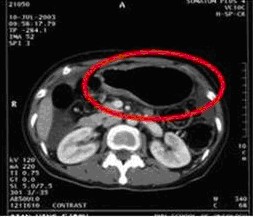

女,49歲。胃體癌晚期,胃竇增厚強(qiáng)化,與周?chē)尺B,腹膜增厚,腹腔廣泛轉(zhuǎn)移,伴大量腹水。放/化療失敗,無(wú)法手術(shù)。治療方案:腹腔灌注今又生2×1012VP/2次/周,共12周,同時(shí)灌注順鉑和5-氟尿嘧啶腹腔,后4周加8次全腹熱療。治療后:第3周,腹水消失;第8周,胃竇、腹膜和網(wǎng)膜變薄,盆腔結(jié)節(jié)明顯變小。后行手術(shù)切除殘余胃腫瘤,術(shù)中探查全腹和盆腔未捫及腫瘤。術(shù)后病檢胃腫瘤內(nèi)未見(jiàn)癌細(xì)胞。

治療中:第8周,腹水消失,胃壁變薄,盆腔結(jié)節(jié)明顯變小